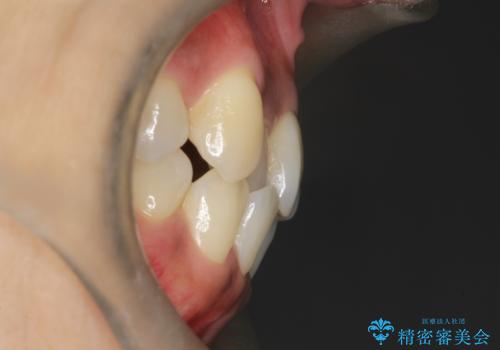

【審美装置】抜歯の本数最小限で行った矯正治療

- 治療計画

- 全体のがたつきを主訴に来院されました。4番目の歯を4本抜歯も検討しましたが、口元が下がりすぎてしまうリスクと2番目の転位うが著しく並べるのにかかる期間を考慮し、変則的な抜歯をし、並べる計画を立てました。

抜歯矯正のため2年はかかってしまいましたが、きれいに並び患者様にも満足頂きました。